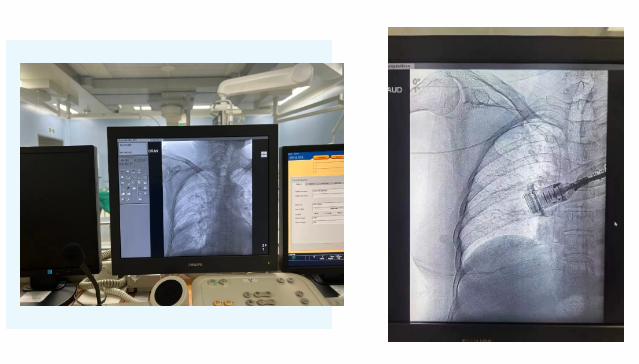

長期靜脈輸液,手臂“不堪重負(fù)”,是很多患者治療中的難題。近日,我院胸腔外科二病區(qū)崔凱主任、支亞男主治醫(yī)師、神經(jīng)外科重癥監(jiān)護(hù)室韓海靜護(hù)士長共同協(xié)作,為一名腫瘤患者完成上臂式靜脈輸液港植入術(shù)。該項(xiàng)手術(shù)的開展標(biāo)志著我院靜脈治療及……